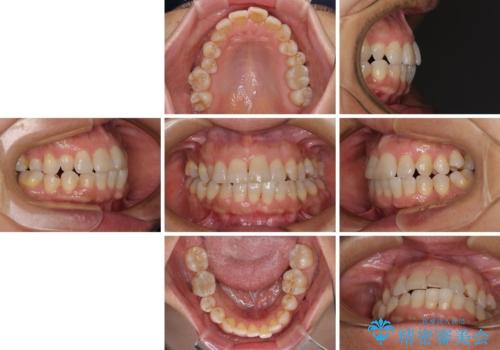

- 骨格的な咬み合わせのズレ、前歯のデコボコとクロスバイトを気にして来院された患者様です。

奥歯の噛みにくさが顕著なためマウスピースではなく、ワイヤー装置による矯正治療を行うこととしました。

下顎の正中を歯1本分ずらした位置とすることで、外見上の骨格的なずれをカバーするように計画しました。

クロスバイトを改善したことで、前歯の負担が軽減し、安定して噛めるようになりました。